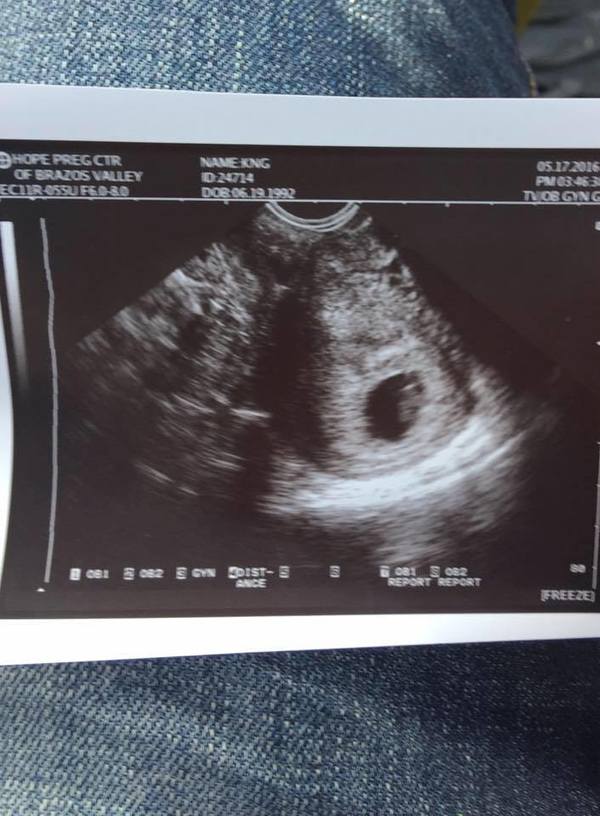

1 Ağustos 2016 tarihinde Kristian ultrasona girdi. Ancak Fabian ile beraber bebeğin cinsiyetini öğrenmek için bir hafta daha beklemeye karar verdiler. The Advertiser’da belirtilenlere göre de bebeğin cinsiyetinin sürpriz şekilde açıklanacağı bir parti düzenlemişler.